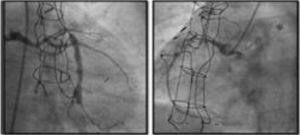

DeviceThe only coronary sinus reducer device currently available and approved for clinical use is the Neovasc Reducer™ (Neovasc Inc., Richmond, BC, Canada). The device consists of a stainless steel mesh mounted in an hourglass-shaped balloon, which after inflation adapts to the tapering conformation of the coronary sinus with two asymmetrical extremities (the proximal larger than the distal) and a narrow central portion that following endothelialization (which takes 4–6 weeks) creates a pressure gradient between the venous circulation corresponding to the territory of the left coronary artery and the right atrium. The semicompliant balloon is available in only one size and the device’s final expanded diameters (9−14 mm) are dependent on the filling pressure, enabling it to adapt to fit the range of anatomies encountered in most patients, while the diameter of the central neck will always be 3 mm (Figure 3).

The device is implanted with a 10-20% oversizing -20 at each end relative to the coronary sinus diameter, in order to anchor the device and to trigger the vascular injury that will induce tissue regrowth and endothelialization.

After implantation, the device can be balloon expanded at any time, so that further interventions can be performed through the coronary sinus if required.

EvidenceSince the coronary sinus Reducer was first used in humans 15 years ago, more than 1000 devices have been implanted worldwide. No long-term complications have been reported.